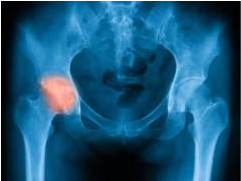

股骨头坏死是什么原因?河南治疗骨科医院为您介绍它

河南治疗骨科医院介绍股骨头坏死是骨科特别常见的一种疾病。股骨头坏死的这种疾病,其实很…[详情]

股骨头坏死的症状有哪些?河南治疗股骨头坏死医院

河南治疗股骨头坏死医院介绍股骨头坏死是较为常见的骨科疾病,多数患者有长期酗酒史、激素…[详情]

郑州骨科病医院:股骨头坏死早期的治疗方法是什么?

郑州骨科病医院介绍股骨头坏死按医学分为Ⅰ、Ⅱ、Ⅲ、Ⅵ期,即通俗说的轻、中、重到更重。…[详情]